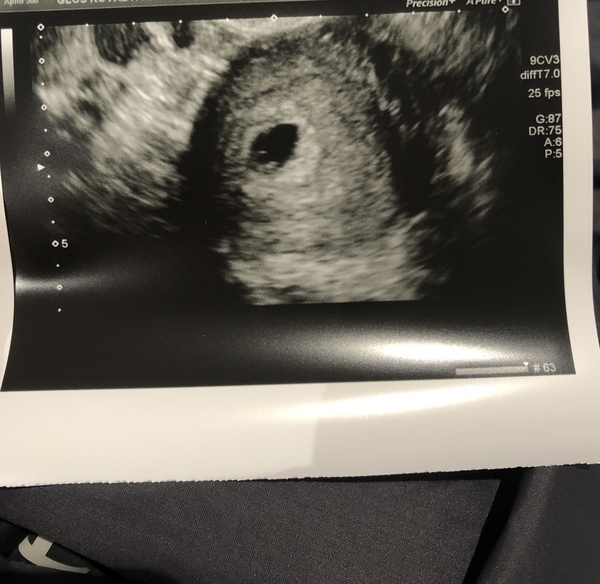

@mumof23188 so after a doctors appointment yesterday, pretty routine one. She did my blood pressure which was sky high. Got talking to her about my anxieties over this pregnancy due to my 4 miscarriages, and she was SO lovely. She said she’d refer me to EPAU for a reassurance scan. Well they phoned me and got me in this afternoon!!!

Was a bit worried as I’m only 5+5 but saw a perfect bean with a gorgeous flickering heartbeat!! I’m measuring bang on.

I felt sick with nerves. They tried abdominal first and saw nothing so I was fearing the worst, but after what felt like forever while she was going the tv scan she turned the screen towards me and showed me the flickering heartbeat. She asked how far I thought I was and I said 5+5 and she said it looks bang on for that. She said she’d have said just under 6 weeks.

@Moominmiss wow I am absolutely over the moon to see your message. I’m so so happy for you ❤️. Beautiful scan picture and how amazing to see your bean and their heartbeat. Strong little bean you have there ☺️. Your GP sounds fantastic I’m so pleased that she listened to your concerns and amazing that the epu got you in so soon.